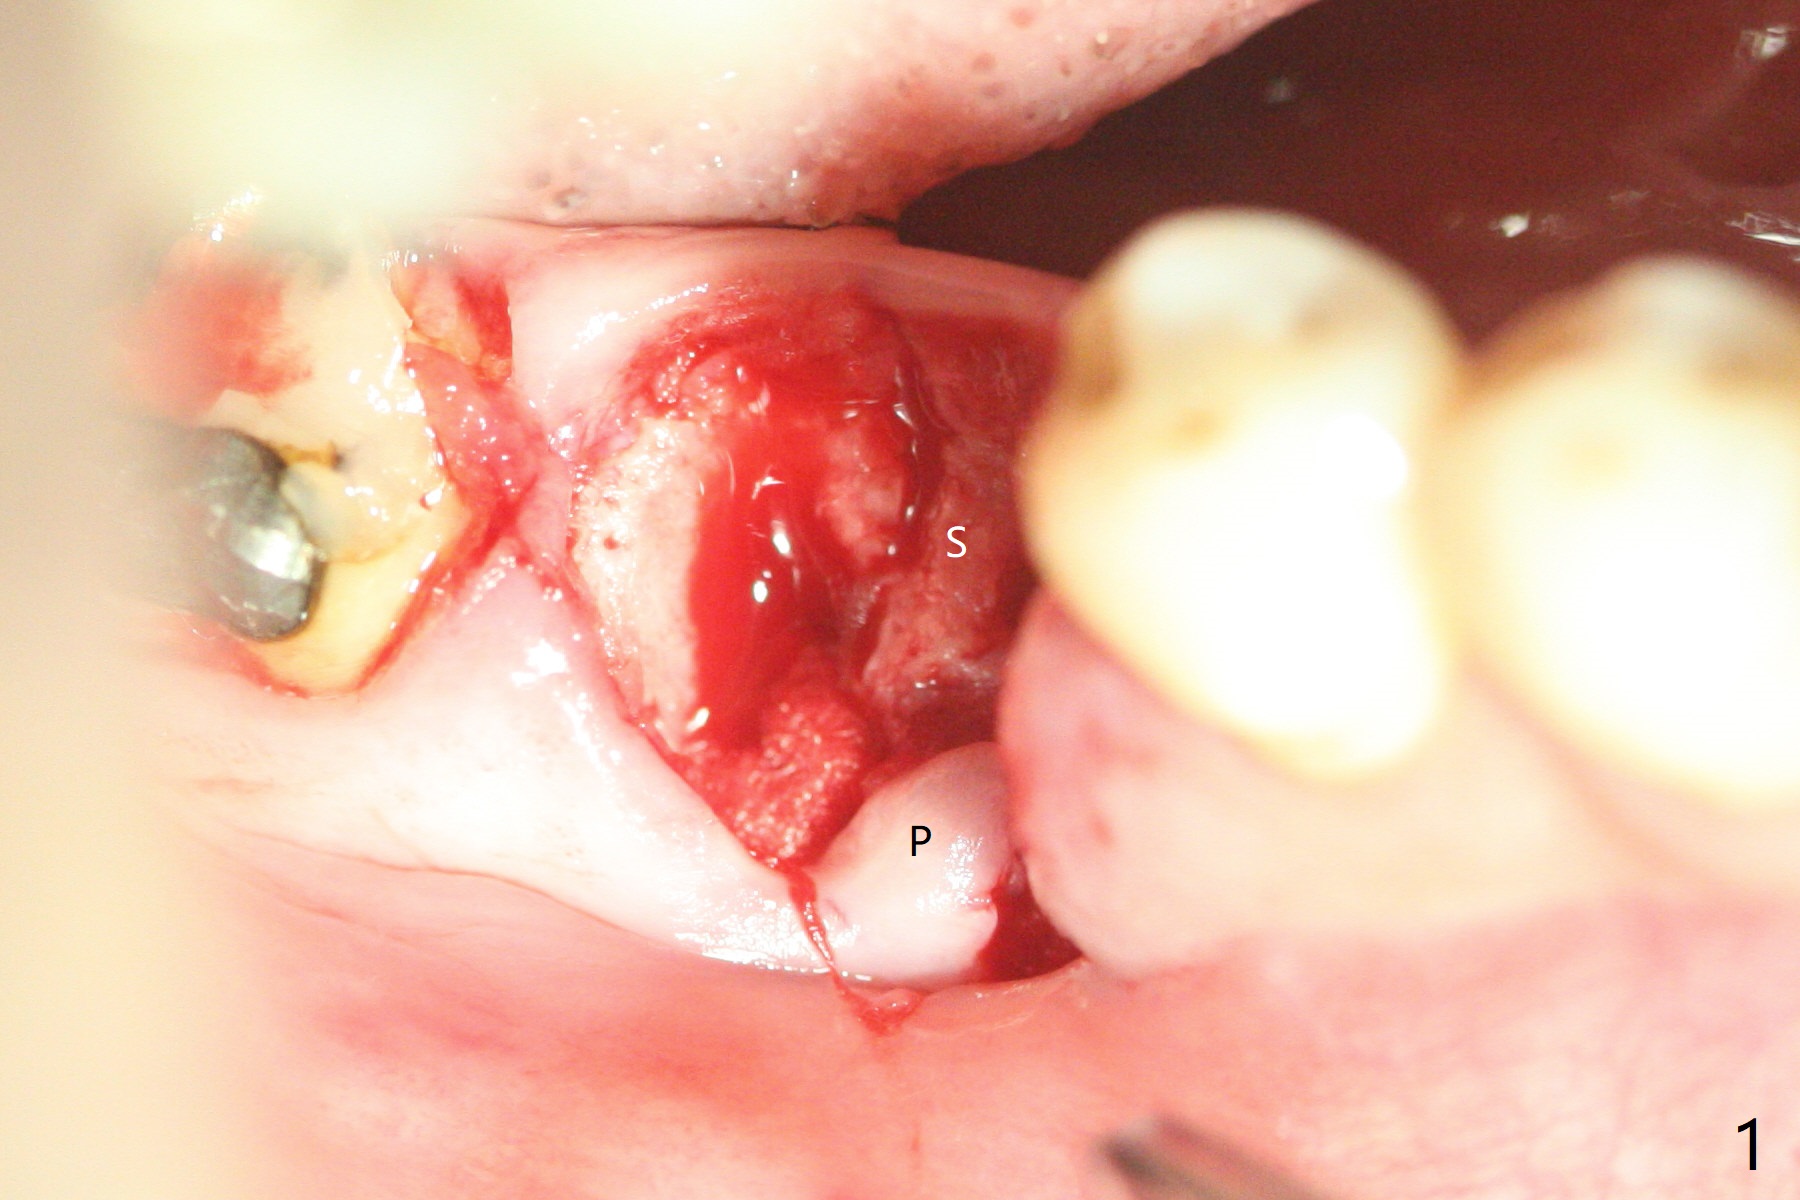

Repair of Extensive Hard and Soft Tissue Defect

When the tooth #30 is extracted, the gingiva buccal to the septum (S in Fig.1,2 (P: papilla between the mesial and distal roots)) collapses. The latter is fixed with placement of a 4.5x11.5 mm implant (with guide), a 5.2x4(5) mm cemented abutment (Fig.3) and mixture of cortical bone (125μm – 850μm) and cortical/cancellous bone (.5-1 mm) with PRF (sticky bone, B in Fig.4-6). After placement of 2 pieces of PRF membrane over the bone graft, a temporary crown is fabricated to cover the buccal defect (Fig.7 T). Approximately 7.5 mm of the buccal threads are covered by the thick layer of bone graft (Fig.8 B). It is amazing to expect that the bone graft will turn into the buccal plate. It would be better if a narrower implant (4 instead of 4.5 mm) were placed more lingually or there were < 4 mm implant thread exposure (Fig.9). The gingiva reacts to the provisional nicely 7 days postop (Fig.10). The provisional will be removed for modification in 1 month. The patient complains of bad smell from the provisional 2 weeks postop. The provisional is removed. The distal socket (Fig.11 D) is healing, whereas the buccal bone graft (Fig.12 B) seems not have been vascularized. Pedicled flaps (I) should be transferred to cover the buccal bone graft. The margin of the provisional is polished, becomes short, and covered by periodontal dressing, which dislodges 2 days later. One week later, granulation tissue is forming apically with use of oral antibiotic and water jet (Fig.13 *). The bad smell reduces. The superficial loose bone graft changes colar and becomes detached 1 month 10 days postop. The temporary crown with the shortened buccal shelf is reseated for self cleansing or reapplication of PRF if needed (Fig.14).